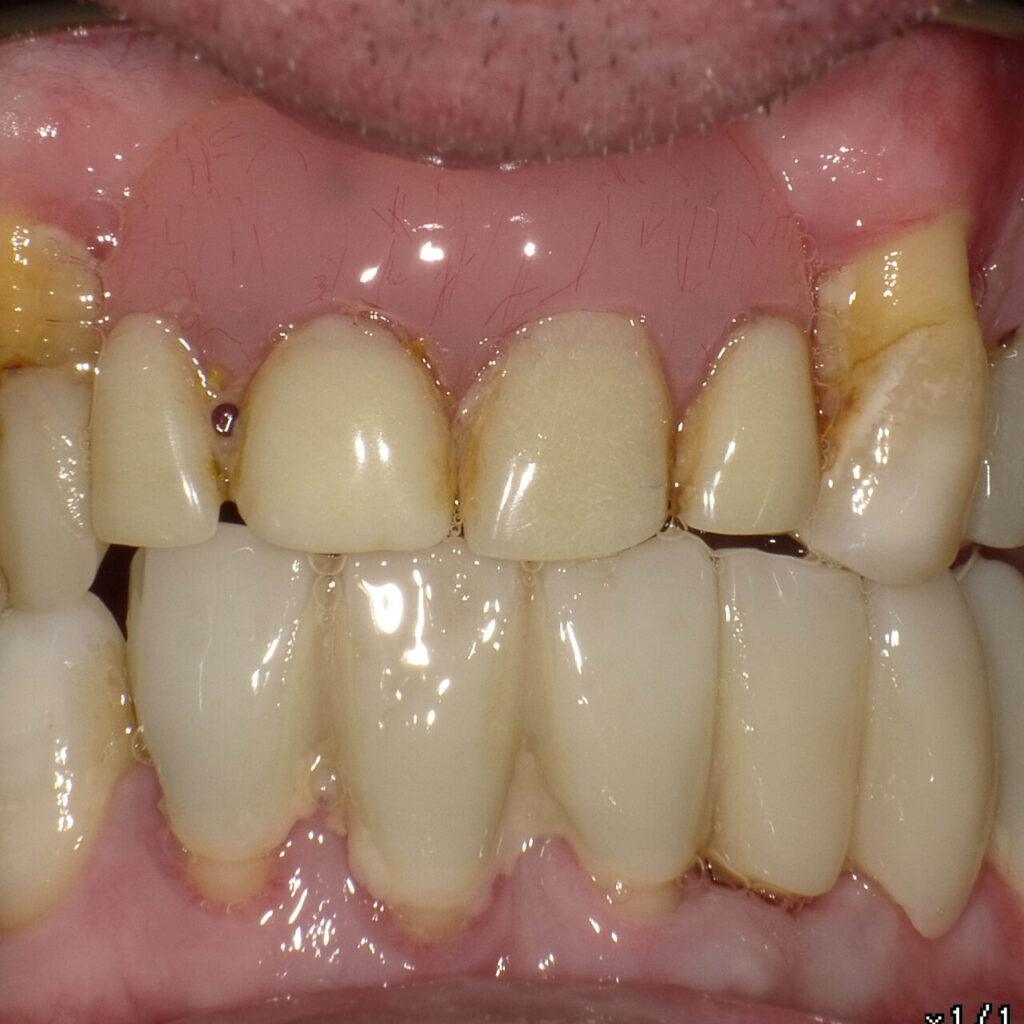

Boisz się jeść przy ludziach, bo proteza może wypaść. Unikasz twardych potraw, które kochasz.

Im dłużej nosisz ruchomą protezę, tym bardziej zanika kość. Implant zatrzymuje ten proces.